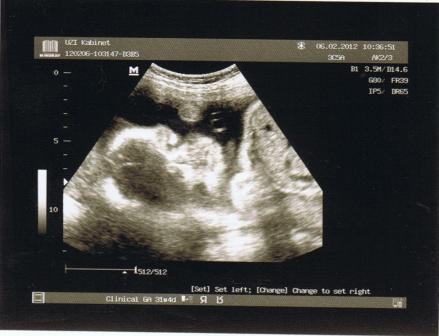

а вот наша первая фотография правда не очень четко видно - тут головка и правая ручка в кулочке сжата...

Сообщение от mixailova Посмотреть сообщение

У меня альбомчик для малыша специальный, там ещё записи делать нужно, так вот на первой странице под надписью "Моя первая фотография" теперь придется эту приклеить!!!

У меня тоже в альбоме Яриковском на страничке моя первая фотография - фото с узи

Кать, фоточка хорошенькая!!!! И правда-первая фотка!!!